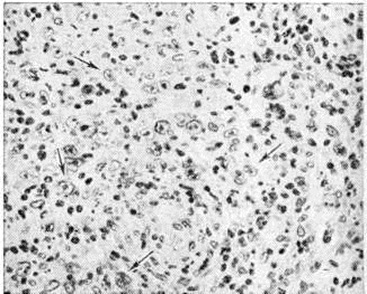

Рис. 3.

Микропрепараты лимфатического узда при лимфогранулематозе с нодулярным склерозом: а виден узел опухолевой ткани, окружённый кольцевидными разрастаниями коллагеновых волокон (указано стрелкой); б видны коллагеновые волокна, импрегнированные азотнокислым серебром (указаны стрелкой); в — лакунарные клетки Березовского Штернберга (указаны стрелками).

Нодулярный склероз характеризуется развитием своеобразных грубоволокнистых кольцевидных прослоек соединительной ткани, разделяющих ткань, например лимфатических, узлов, на отдельные узелки (рисунок 3, а, б) с клеточным составом, соответствующим лимфогистиоцитарному и смешанно-клеточному типам, а также ретикулярному варианту Лимфогранулематоз Морфологически особенностью нодулярного склероза является частое преобладание в опухолевой ткани лакунарных клеток Березовского—Штернберга (рисунок 3, в).

Для лимфоидного истощения при диффузном фиброзе характерно выраженное беспорядочное развитие соединительной ткани и уменьшение общего числа клеток прежде всего за счёт лимфоцитов (рисунок 4). Ретикулярный вариант характеризуется выраженной пролиферацией атипичных гистиоцитов (рисунок 5) и клеток Березовского—Штернберга.